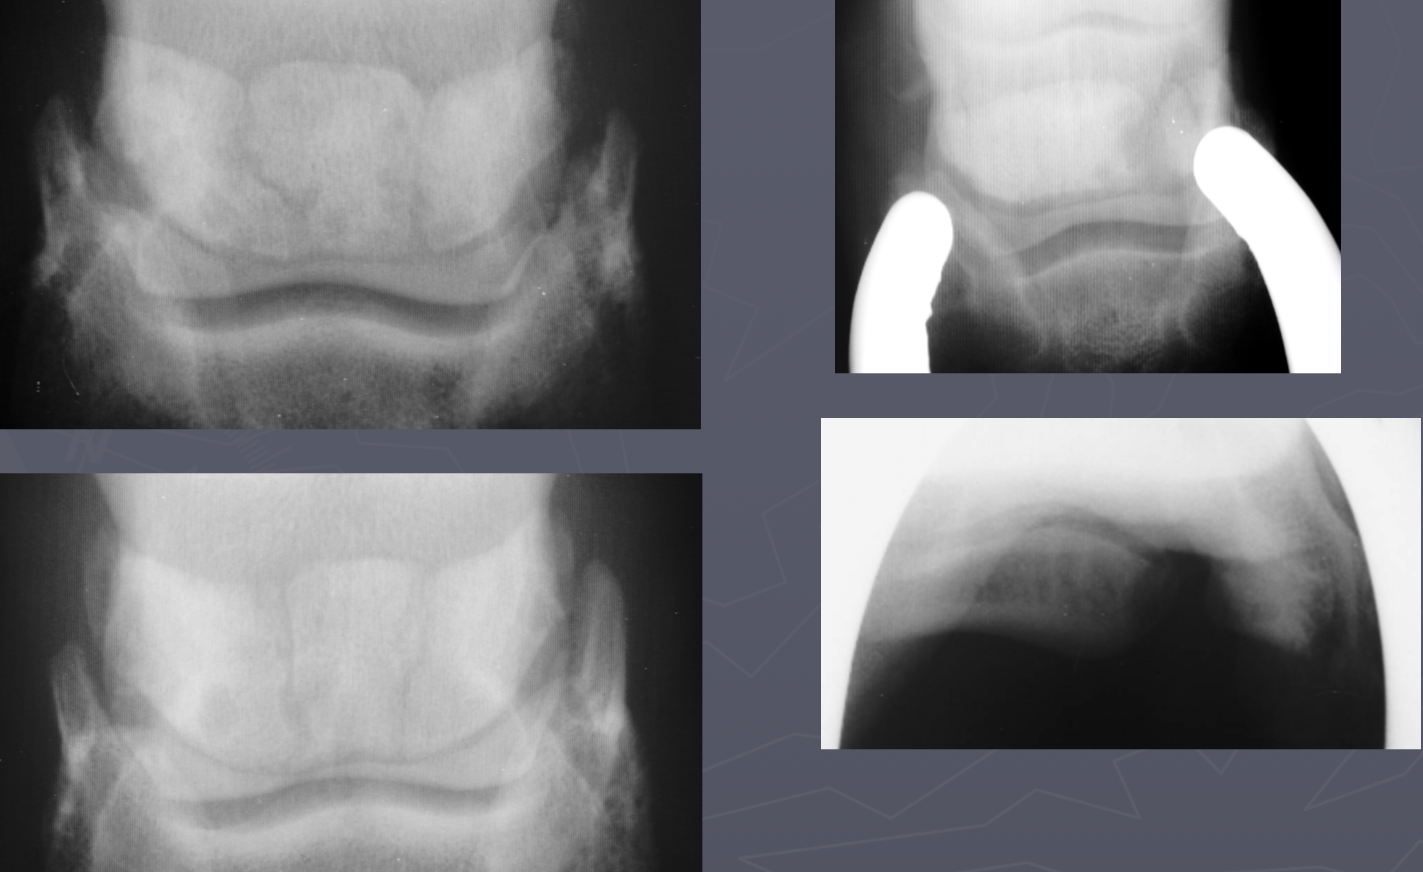

DJD